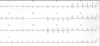

Interpret the tracing in A and B

- A) 1st degree AV block w/ non-conducted PAC

- B) 1st degree AV block w/ non-conducted PAC occurring in trigeminal rhythm